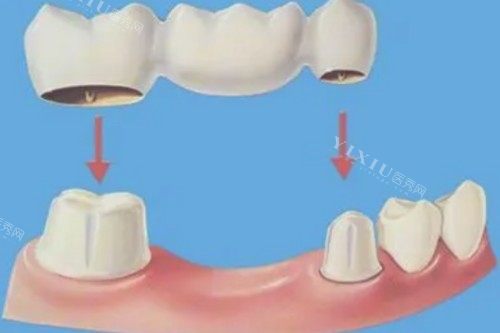

镶假牙

树脂活动假牙:630元起/副

吸附性义齿:6299元起/副

钴铬合金烤瓷牙:800元起/颗

纯钛烤瓷牙:1000元起/颗

国产全瓷牙:1200元起/颗

进口全瓷牙:2700元起/颗

单颗全瓷冠:2500元起/颗

半固定假牙:15000元起/副